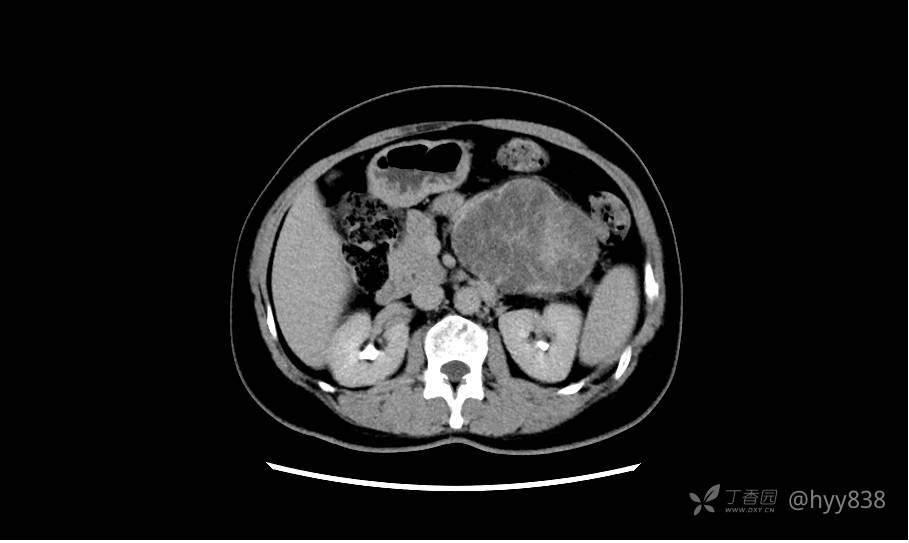

静脉期(机器故障---延迟期了)